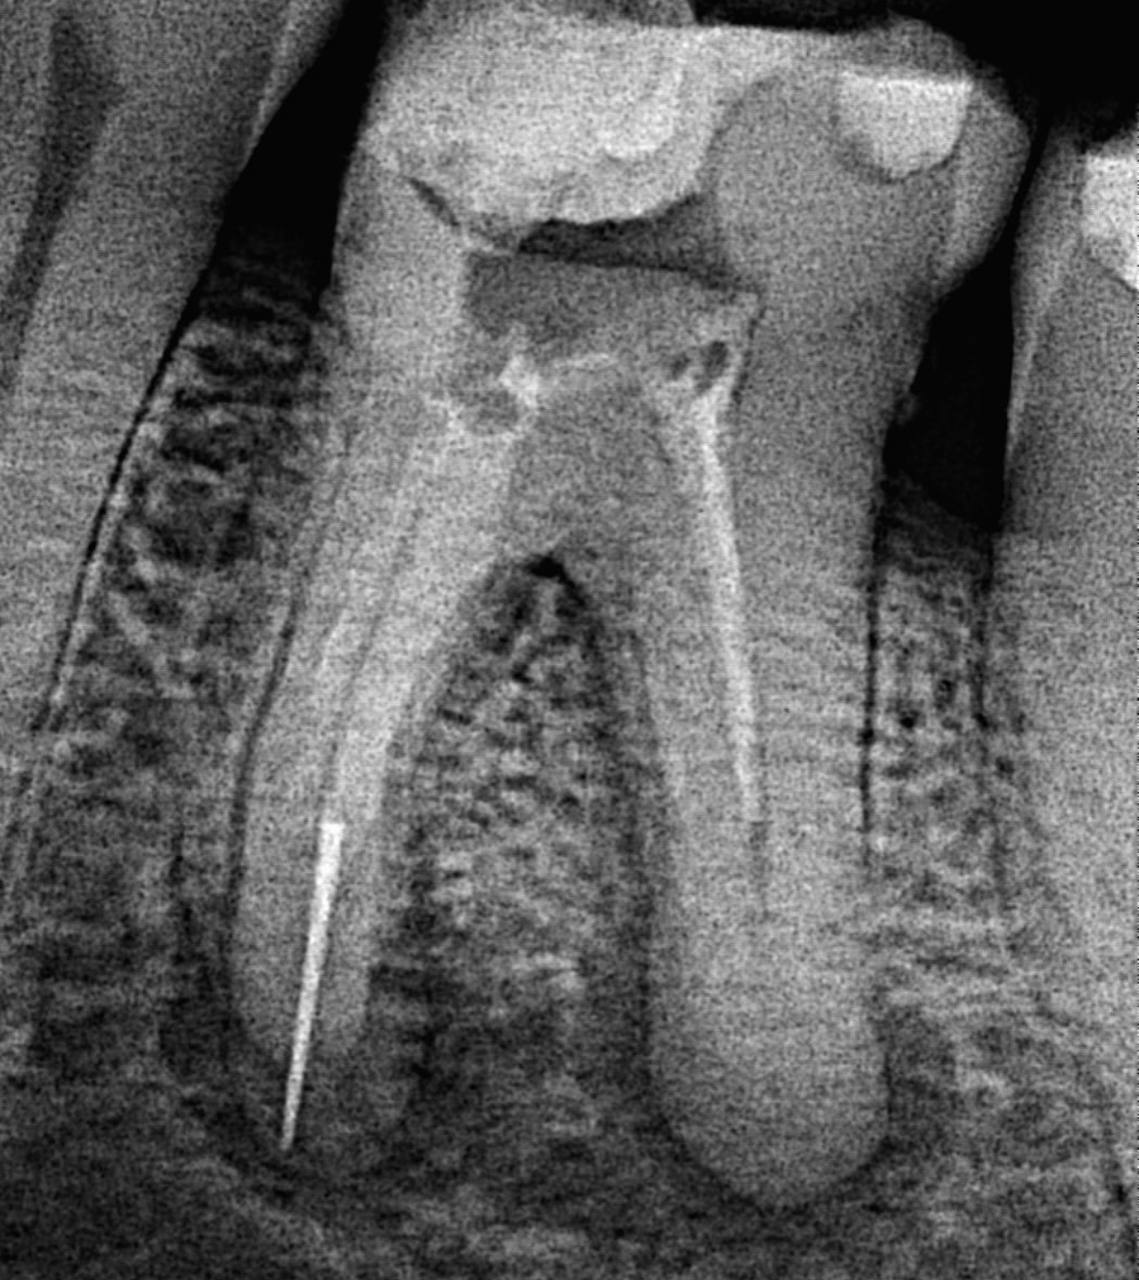

4. What type of perforation is being treated by an endodontist in this X ray?